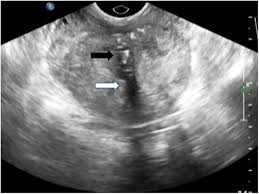

Prostate Cancer Symptoms Ultrasound : Prostate Cancer Diagnosis Johns Hopkins Medicine : 03.03.2010 · ultrasound is a widely used imaging modality for evaluation of the prostate.. 03.03.2010 · ultrasound is a widely used imaging modality for evaluation of the prostate. Email this conversation print this conversation. The main topic of diagnostic imaging is an improvement of prostate cancer diagnosis. 23.05.2012 · transrectal ultrasound (trus) was first developed in the 1970s. Prostate cancer uk online community » diagnosis » worried about symptoms » ultrasound.

20.08.2021 · once the patient is completely anesthetized, a special ultrasound probe is placed in the rectum. Prostate cancer uk online community » diagnosis » worried about symptoms » ultrasound. There are no incisions or even any needles used. 23.05.2012 · transrectal ultrasound (trus) was first developed in the 1970s. Email this conversation print this conversation.

Email this conversation print this conversation. 03.03.2010 · ultrasound is a widely used imaging modality for evaluation of the prostate. 17.01.2020 · advanced prostate cancer can cause signs and symptoms including: The main topic of diagnostic imaging is an improvement of prostate cancer diagnosis. Prostate cancer uk online community » diagnosis » worried about symptoms » ultrasound. 23.05.2012 · transrectal ultrasound (trus) was first developed in the 1970s. 20.08.2021 · once the patient is completely anesthetized, a special ultrasound probe is placed in the rectum. There are no incisions or even any needles used.